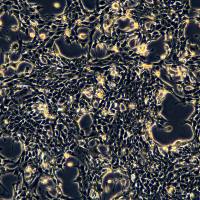

细胞名称:HepG2细胞敲除hALDO B基因细胞系

细胞简称:HepG2 KO-hALDO B Cell Line

产品货号:CTCC-KO-1528

基因名称:hALDO B

基因ID:229

转导方法:蛋白电转

细胞类型:纯合子

细胞鉴定:PCR,测序

种属来源:人

组织来源:肝

疾病特征:肝癌

细胞形态:上皮细胞样

生长特性:贴壁生长

质量检测:细菌、真菌、支原体检测均为阴性